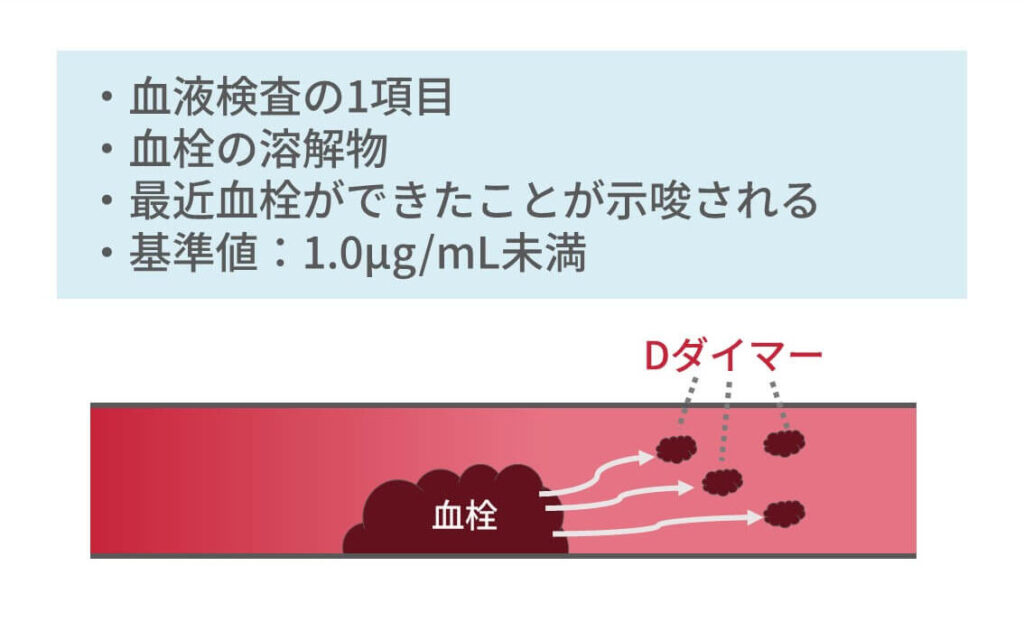

診断プロセス中に臨床検査も使用されます。ただし、彼らだけでは頸静脈血栓症を確認したり除外したりすることはできません。医療専門家が注文する臨床検査の例としては、次のようなものがあります。